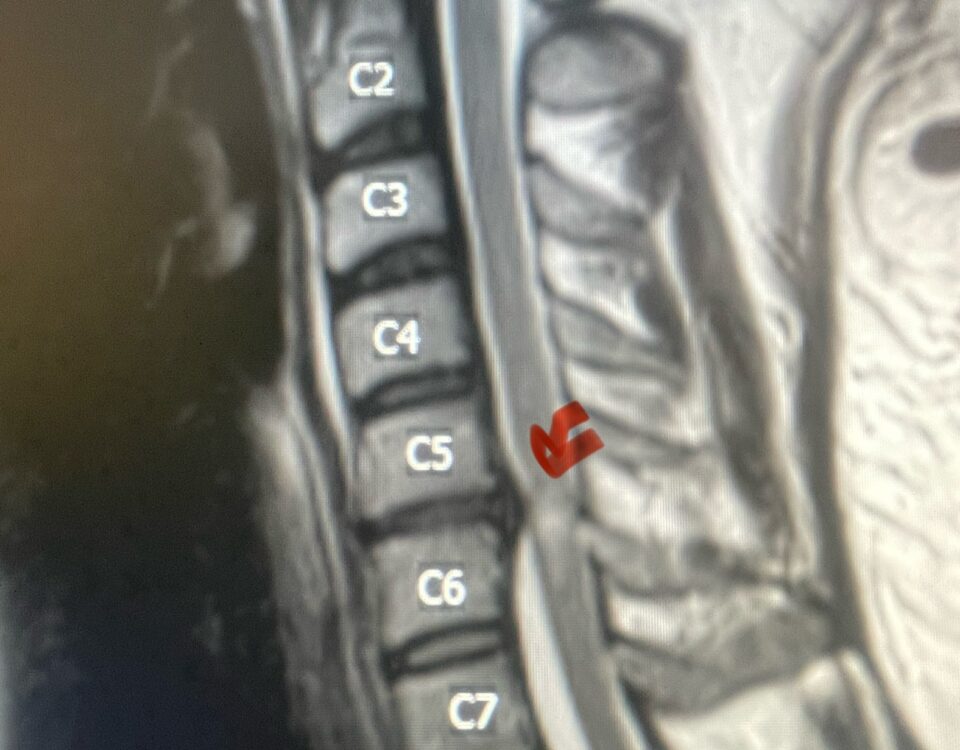

Thoracic stenosis is far less common than lumbar stenosis. Whereas the symptoms of lumbar stenosis are usually well-defined, thoracic stenosis can act like a great mimicker, […]

Nervous tissue is soft. The thecal sac is surrounded by a rigid bony ring which forms the spinal canal. Any mass that fills the very small […]